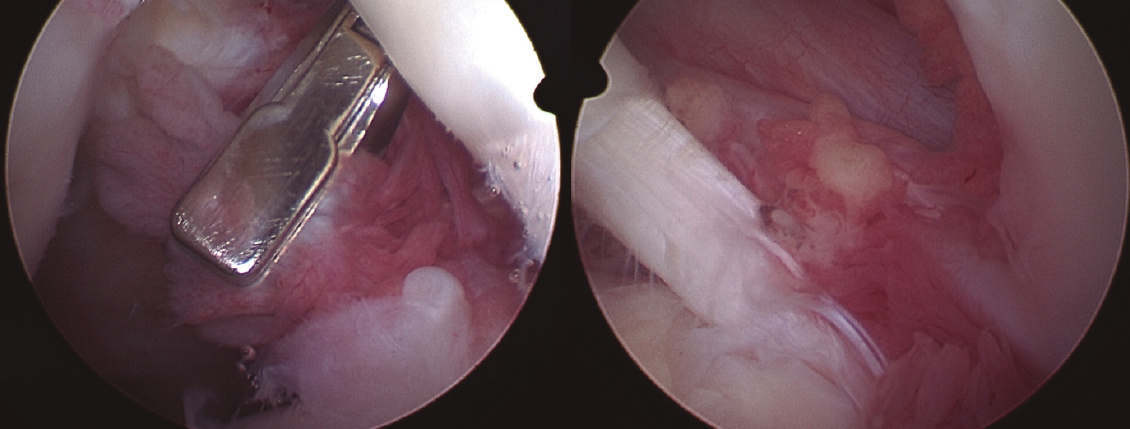

En todos los casos se remitieron muestras de biopsia al Servicio de Anatomía Patológica (Figura 5). Se realizó, por tanto, una sinovectomía amplia y electrocauterización. En los casos de hombro en los que existía una rotura del supraespinoso suturable, se procedió a su reinserción. En un caso, ante una rotura masiva retraída, se decidió llevar a cabo una reconstrucción capsular superior. En los casos de rodilla, en un caso el desbridamiento y exéresis artroscópica fue suficiente al no existir lesiones asociadas, mientras que en el otro caso, ante la degeneración articular y la edad del paciente, se realizó un desbridamiento en el contexto de la implantación de una prótesis total de rodilla.

Figura 5. Imágenes de la toma de biopsia del LA durante la artroscopia de hombro, ubicada en la zona de la periferia del anclaje glenoideo de labrum y porción larga del bíceps, en el que cabe destacar una banda fibrosa a modo de envoltura.